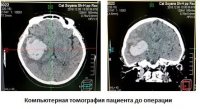

Нейрохирурги Тувы впервые малоинвазивной операцией растворили инсультную внутримозговую гематому

Нейрохирурги Тувы впервые малоинвазивной операцией растворили инсультную внутримозговую гематомуВ Туве нейрохирурги Ресбольницы №1 впервые выполнили малоинвазивное оперативное лечение инсультной внутримозговой гематомы методом аспирации и локального фибринолиза. Фибринолиз – это процесс растворения тромбов и сгустков крови.

Это один из малотравматичных методов эвакуации внутримозговых гематом (ВМГ).